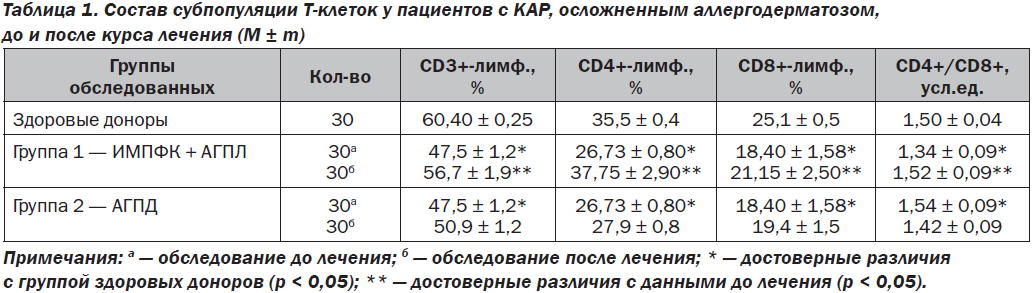

Анализ изменений состояния клеточного иммунитета обследованных больных показал, что у пациентов всех групп был определен достоверно более высокий уровень относительного числа Т-клеток. У пациентов, лечившихся ИМПФК + АГПЛ, после окончания терапии отмечалось достоверное повышение числа Т-клеток по сравнению с пациентами, лечившимися при помощи базисной терапии АГПД. У лиц конт–рольной группы наблюдалась лишь тенденция к увеличению числа Т-клеток.

Выраженность РБТЛ на ФГА у пациентов была существенно ниже нормы и достоверно не различалась в 1-й и 2-й группах (р < 0,05). После проведенной терапии отмечалось достоверное повышение интенсивности бласттрансформации лимфоцитов на ФГА. К концу лечения у пациентов наблюдалась наиболее высокая интенсивность бластообразования неспецифическим митогеном, что подтверждалось повышением функциональной активности Т-лимфоцитов у пациентов, лечившихся ИМПФК + АГПЛ, по сравнению с теми пациентами, которые лечились базисной терапией АГПД.